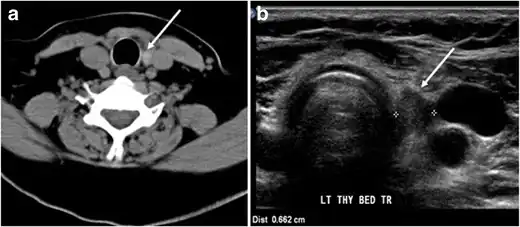

Fig. 15. A 33-year-old female patient who presented with neck swelling and pain and was later diagnosed with Hashimoto's thyroiditis. an Axial enhanced CT scan of the neck demonstrates minimal diffuse enlargement of the thyroid gland, especially the isthmus (white arrow). b Transverse greyscale ultrasound of the neck demonstrates heterogeneously enlarged thyroid and thickened isthmus, measuring 8.6 mm.[1]

Malignancy can coexist within the goiter and a CT scan may give a clue if there are abnormal cervical lymph nodes and/or signs of invasion. Retrosternal extension (Fig. 15) could affect the surgical approach, as a lower extent may require a partial or total sternotomy to facilitate complete resection. Therefore, the distance of the retrosternal extent from the sternal notch should be measured on a sagittal image.[1]

Inflammatory lesions

Inflammatory thyroid disorders include acute infectious thyroiditis, Hashimoto's thyroiditis, Riedel's thyroiditis, and granulomatous thyroiditis (de Quervain's). Hashimoto's thyroiditis is associated with an increased risk of lymphoma and papillary thyroid carcinoma. The CT scan findings of thyroiditis are nonspecific and variable (Figs. 14, 1515 and and16)16). The thyroid gland has a very high iodine concentration, resulting in high CT attenuation (80–100 Hounsfield Units). The presence of thyroiditis can be suggested by a diffusely enlarged and hypo-attenuating (around 45 Hounsfield Units) thyroid gland. This is probably due to follicular cell destruction and reduced thyroid iodine concentration. Marked homogeneous enhancement is typically expected. Therefore, moderate thyroid enhancement in a case of thyroiditis suggests a diffuse inflammatory process. It is essential to clinically correlate this with a thyroid function test and serum autoantibody levels.[1]